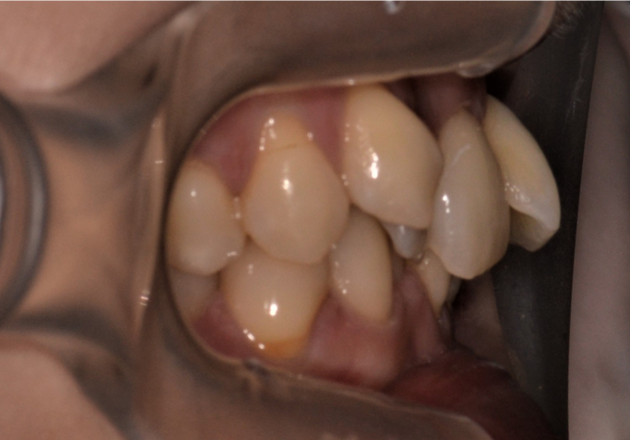

症例1

| 項目 | 詳細 |

|---|---|

| 患者様データ | 30代 女性 |

| 来院時の主訴 | 「上下のガタガタ歯並びと噛み合わせが気になる。」 |

| 矯正法 | 上の歯2本を抜歯しての矯正 |

| 通院期間 | 2年9ヶ月 |

| 治療費 | 総額:1,070,000円(税抜) 【内訳】 精密検査50,000円、メタルワイヤー矯正800,000円、月に1度の調整料5,000円、後戻り防止のリテーナー35,000円×2 |

| リスクと副作用 |

①歯を動かす事による痛みがあります。また、装置に慣れるまでは、口内炎ができやすいです。 ②歯肉が退縮するリスクがあります。装置が全ての歯に付くので、ハミガキが難しくなります。 ③長期的なメインテナンスが必要 |

| ここがこだわりのポイント!☝ |

この患者様の場合、歯並びのガタガタが強かったことや、抜歯したスペースを埋めるのに時間がかりました。ホームケアも大変だったと思いますが、とてもきれいな歯並びに改善することができました。 |